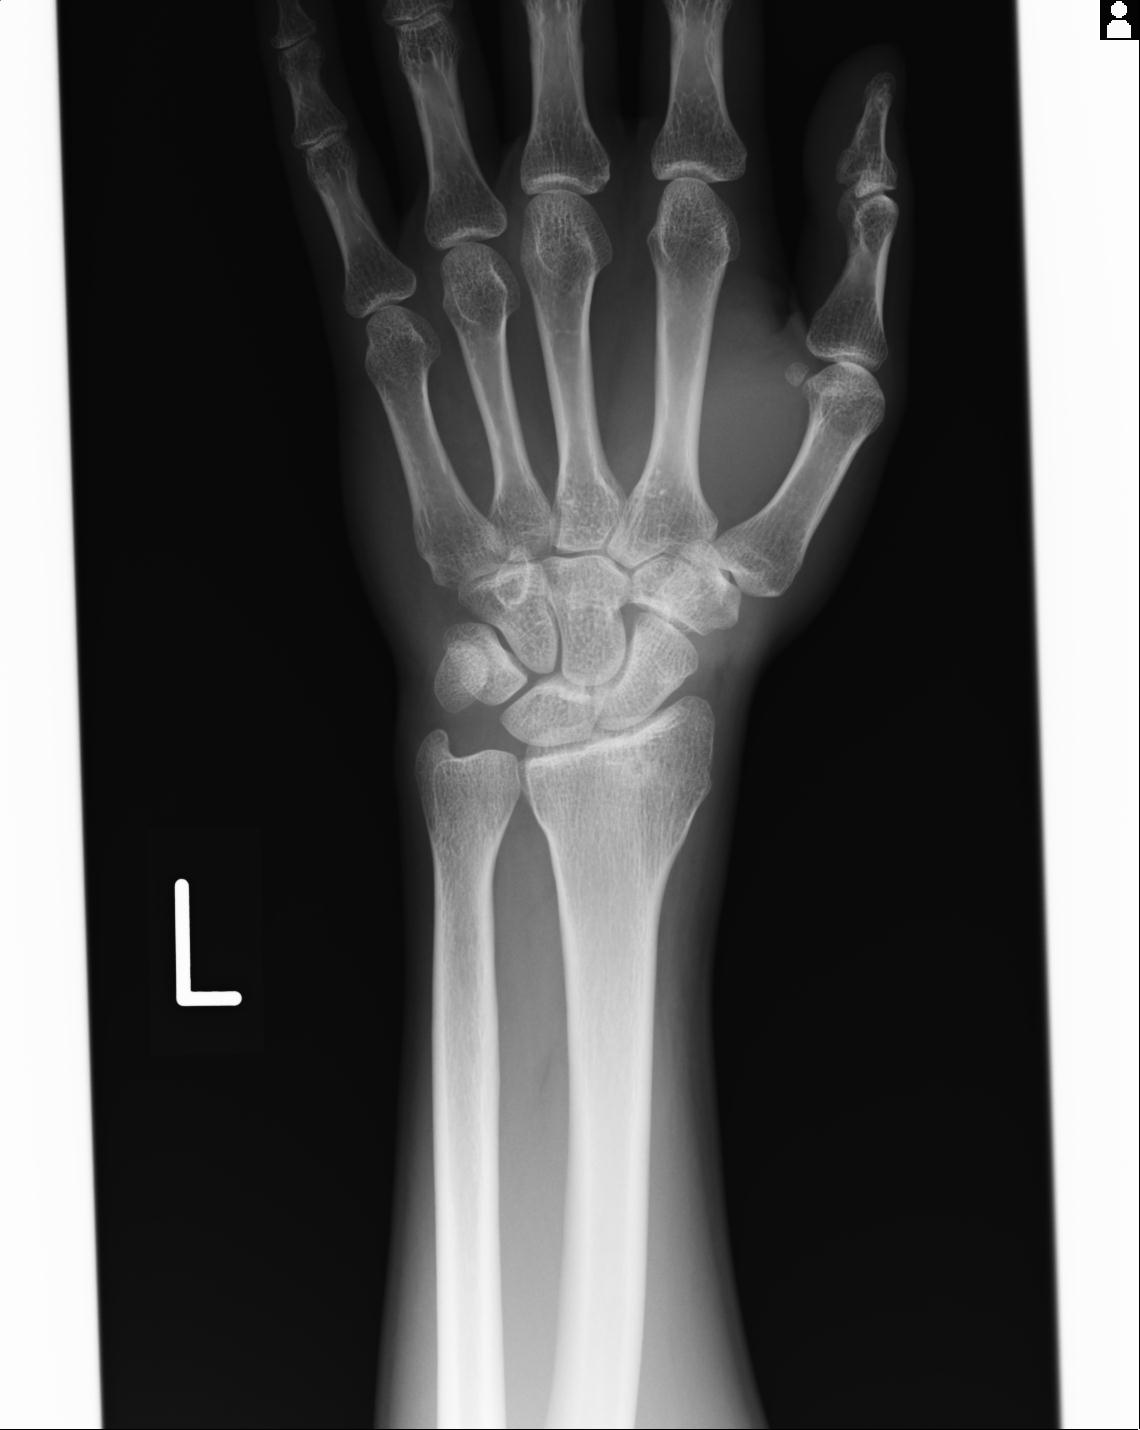

102766 1/5 1/12 左手関節 4R 28歳男性 左橈骨遠位端